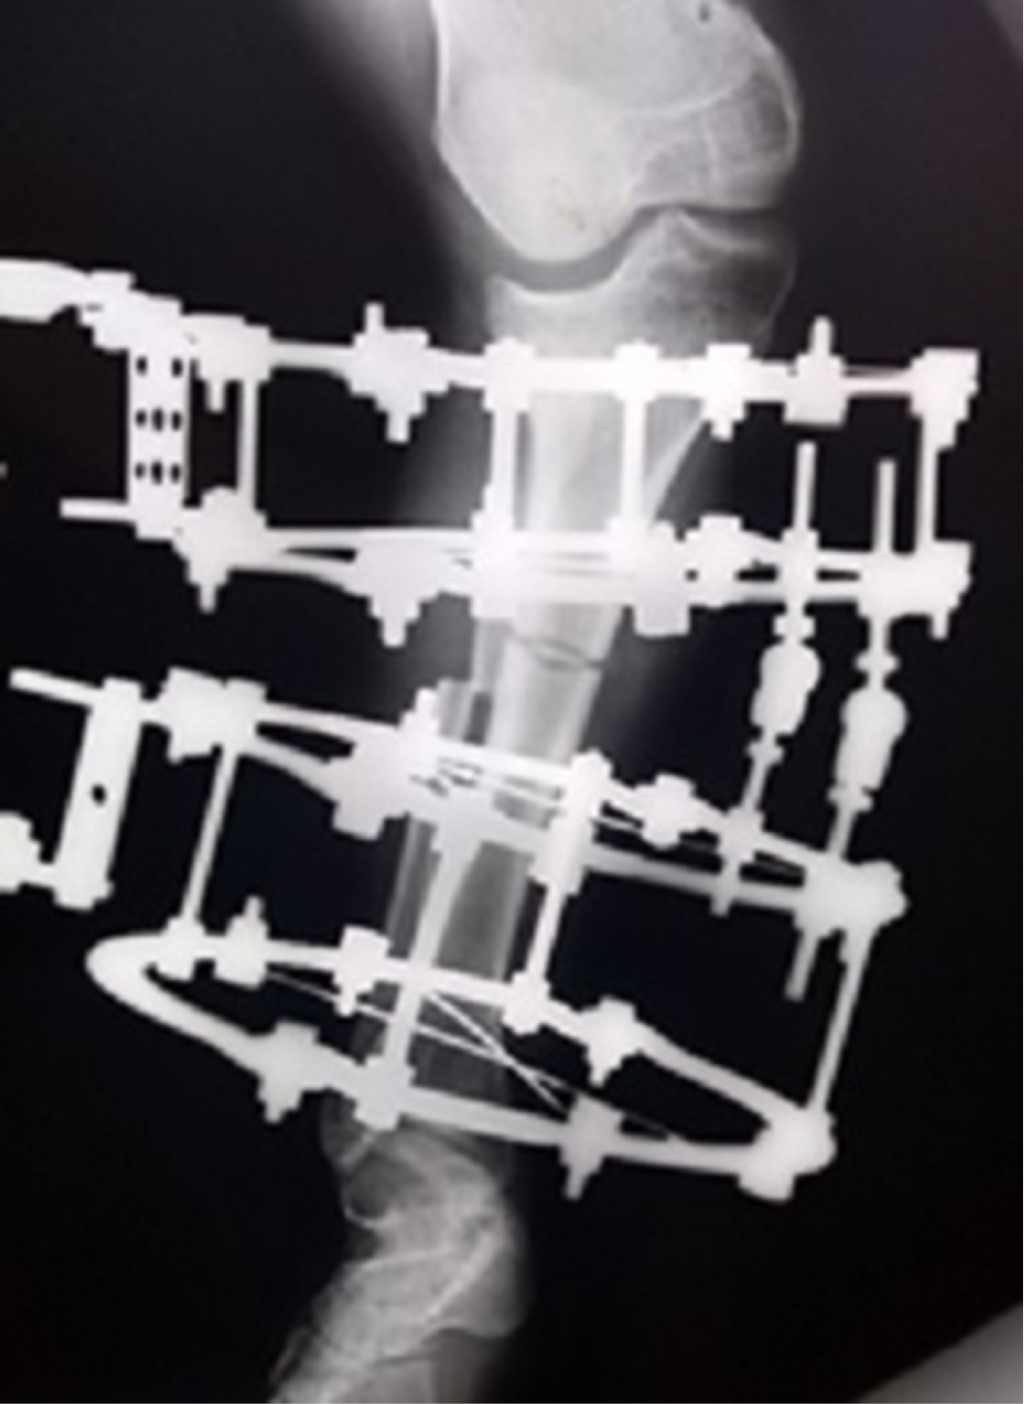

Para la planeación de la cirugía se tomó en cuenta que ambas extremidades contaban con una deformidad ósea compleja. Sin embargo, se observó mayor deformidad en miembro pélvico derecho, además de que el paciente contaba con mayor sintomatología en dicha extremidad. Se inició la primera intervención en tibia derecha a la edad de 15.4 años con una planeación preoperatoria, en la cual se realizó la medición del CORA (Center of Rotation of Angulation) con posterior osteotomía por debajo del mismo, considerando que éste se encontraba a nivel articular, se colocaron las bisagras en la cara convexa de la deformidad y con dos niveles proximales y dos distales para mantener la estabilidad del dispositivo. Se optó por una corrección progresiva con fijador circular Ilizarov para lograr una corrección gradual de la deformidad en valgo. Se realizó una cuña de apertura lateral que medializa y alinea el segmento distal, mejorando el trayecto del aparato extensor y la función de la articulación femoropatelar al lograr hacer paralelas las superficies articulares de la tibia (Figura 2).

Figura 2